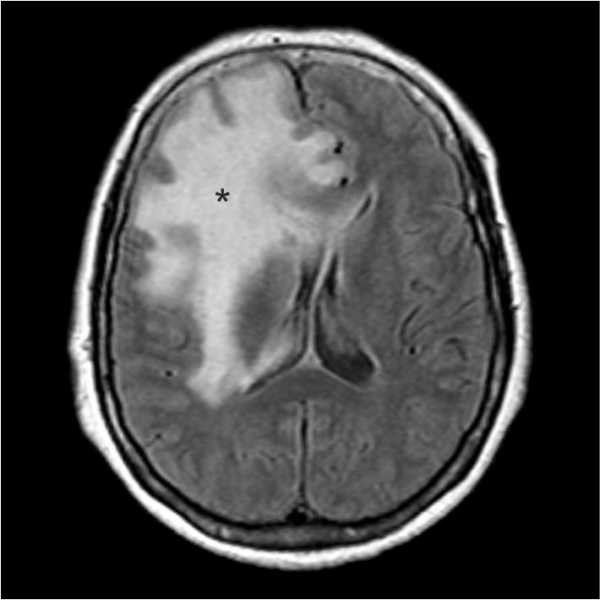

На снимке отек мозга:

Вследствие гематомы: а. На КТ; Б. На МРТ.

Из-за накопления жидкости в тканях мозга, происходит давление внутри, возникает отек.